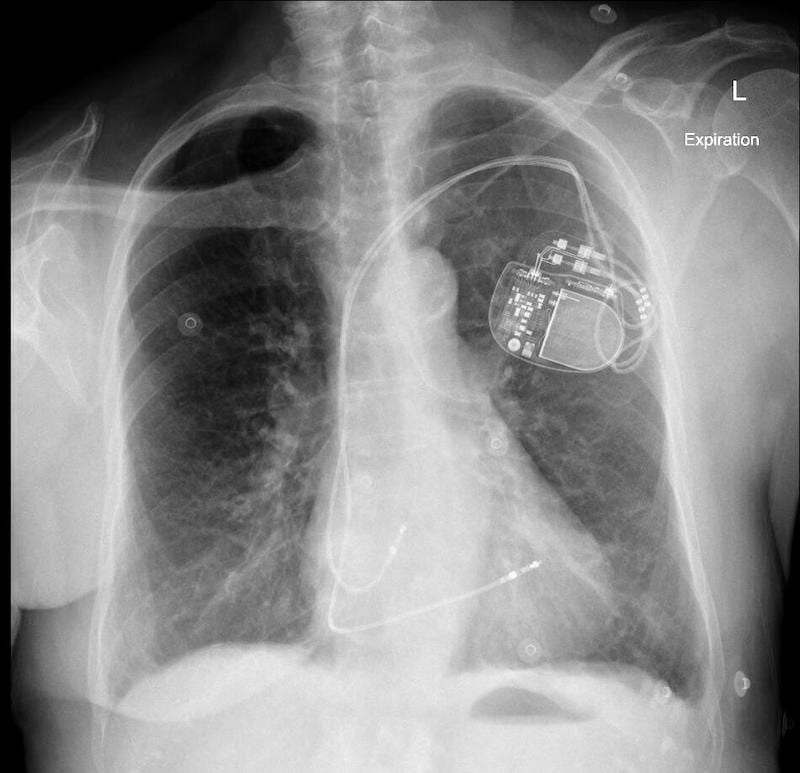

Normal PPM Lead Placement CXR

The following PA and lateral CXR are taken from an unrelated case with appropriately placed pacing leads in the right atrium and right ventricle.

- Note the PA CXR appearance is not too different from the PA CXR in our case of lead misplacement

- Note on the lateral CXR both leads are placed anteriorly signifying right sided placement.

- Side-by-side comparison of cardiac silhouettes. Abnormal on left. Normal on right.